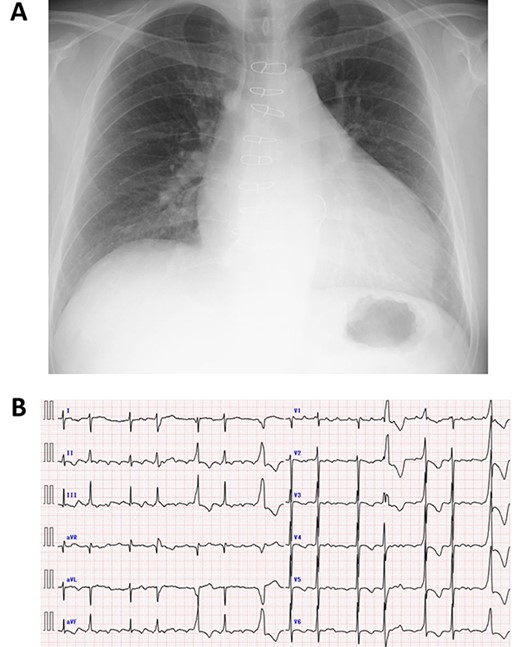

A 50-year-old male who had undergone MV repair 14 years ago due to traumatic mitral valve regurgitation was presented to our department due to heart failure with New York Heart Association (NYHA) III classification. Chest X-ray showed moderate cardiomegaly, and electrocardiogram showed atrial fibrillation with controlled heart rate (Fig. 1A and B). Transthoracic echocardiogram showed moderate MR with severely impaired bi-ventricular function; left ventricular ejection fraction of 20%, (Fig. 2A and B). Coronary angiography showed no significant stenosis. Although indication for mitral valve surgery was marginal [2], surgical intervention was decided to prevent further deterioration of bi-ventricular function.

Preoperative echocardiography of left ventricle in systolic (A) and diastolic (B) phases.